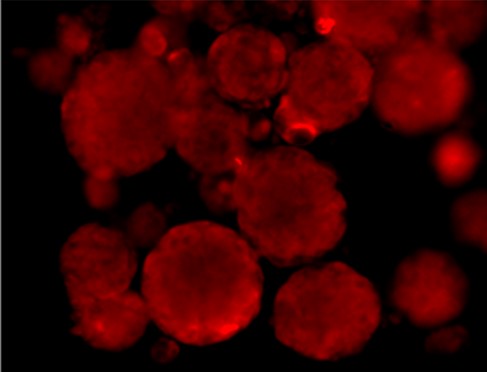

Immunofluorescence staining of Src and Phospho-Src

SRC total

P-SRC Tyr416

Merged